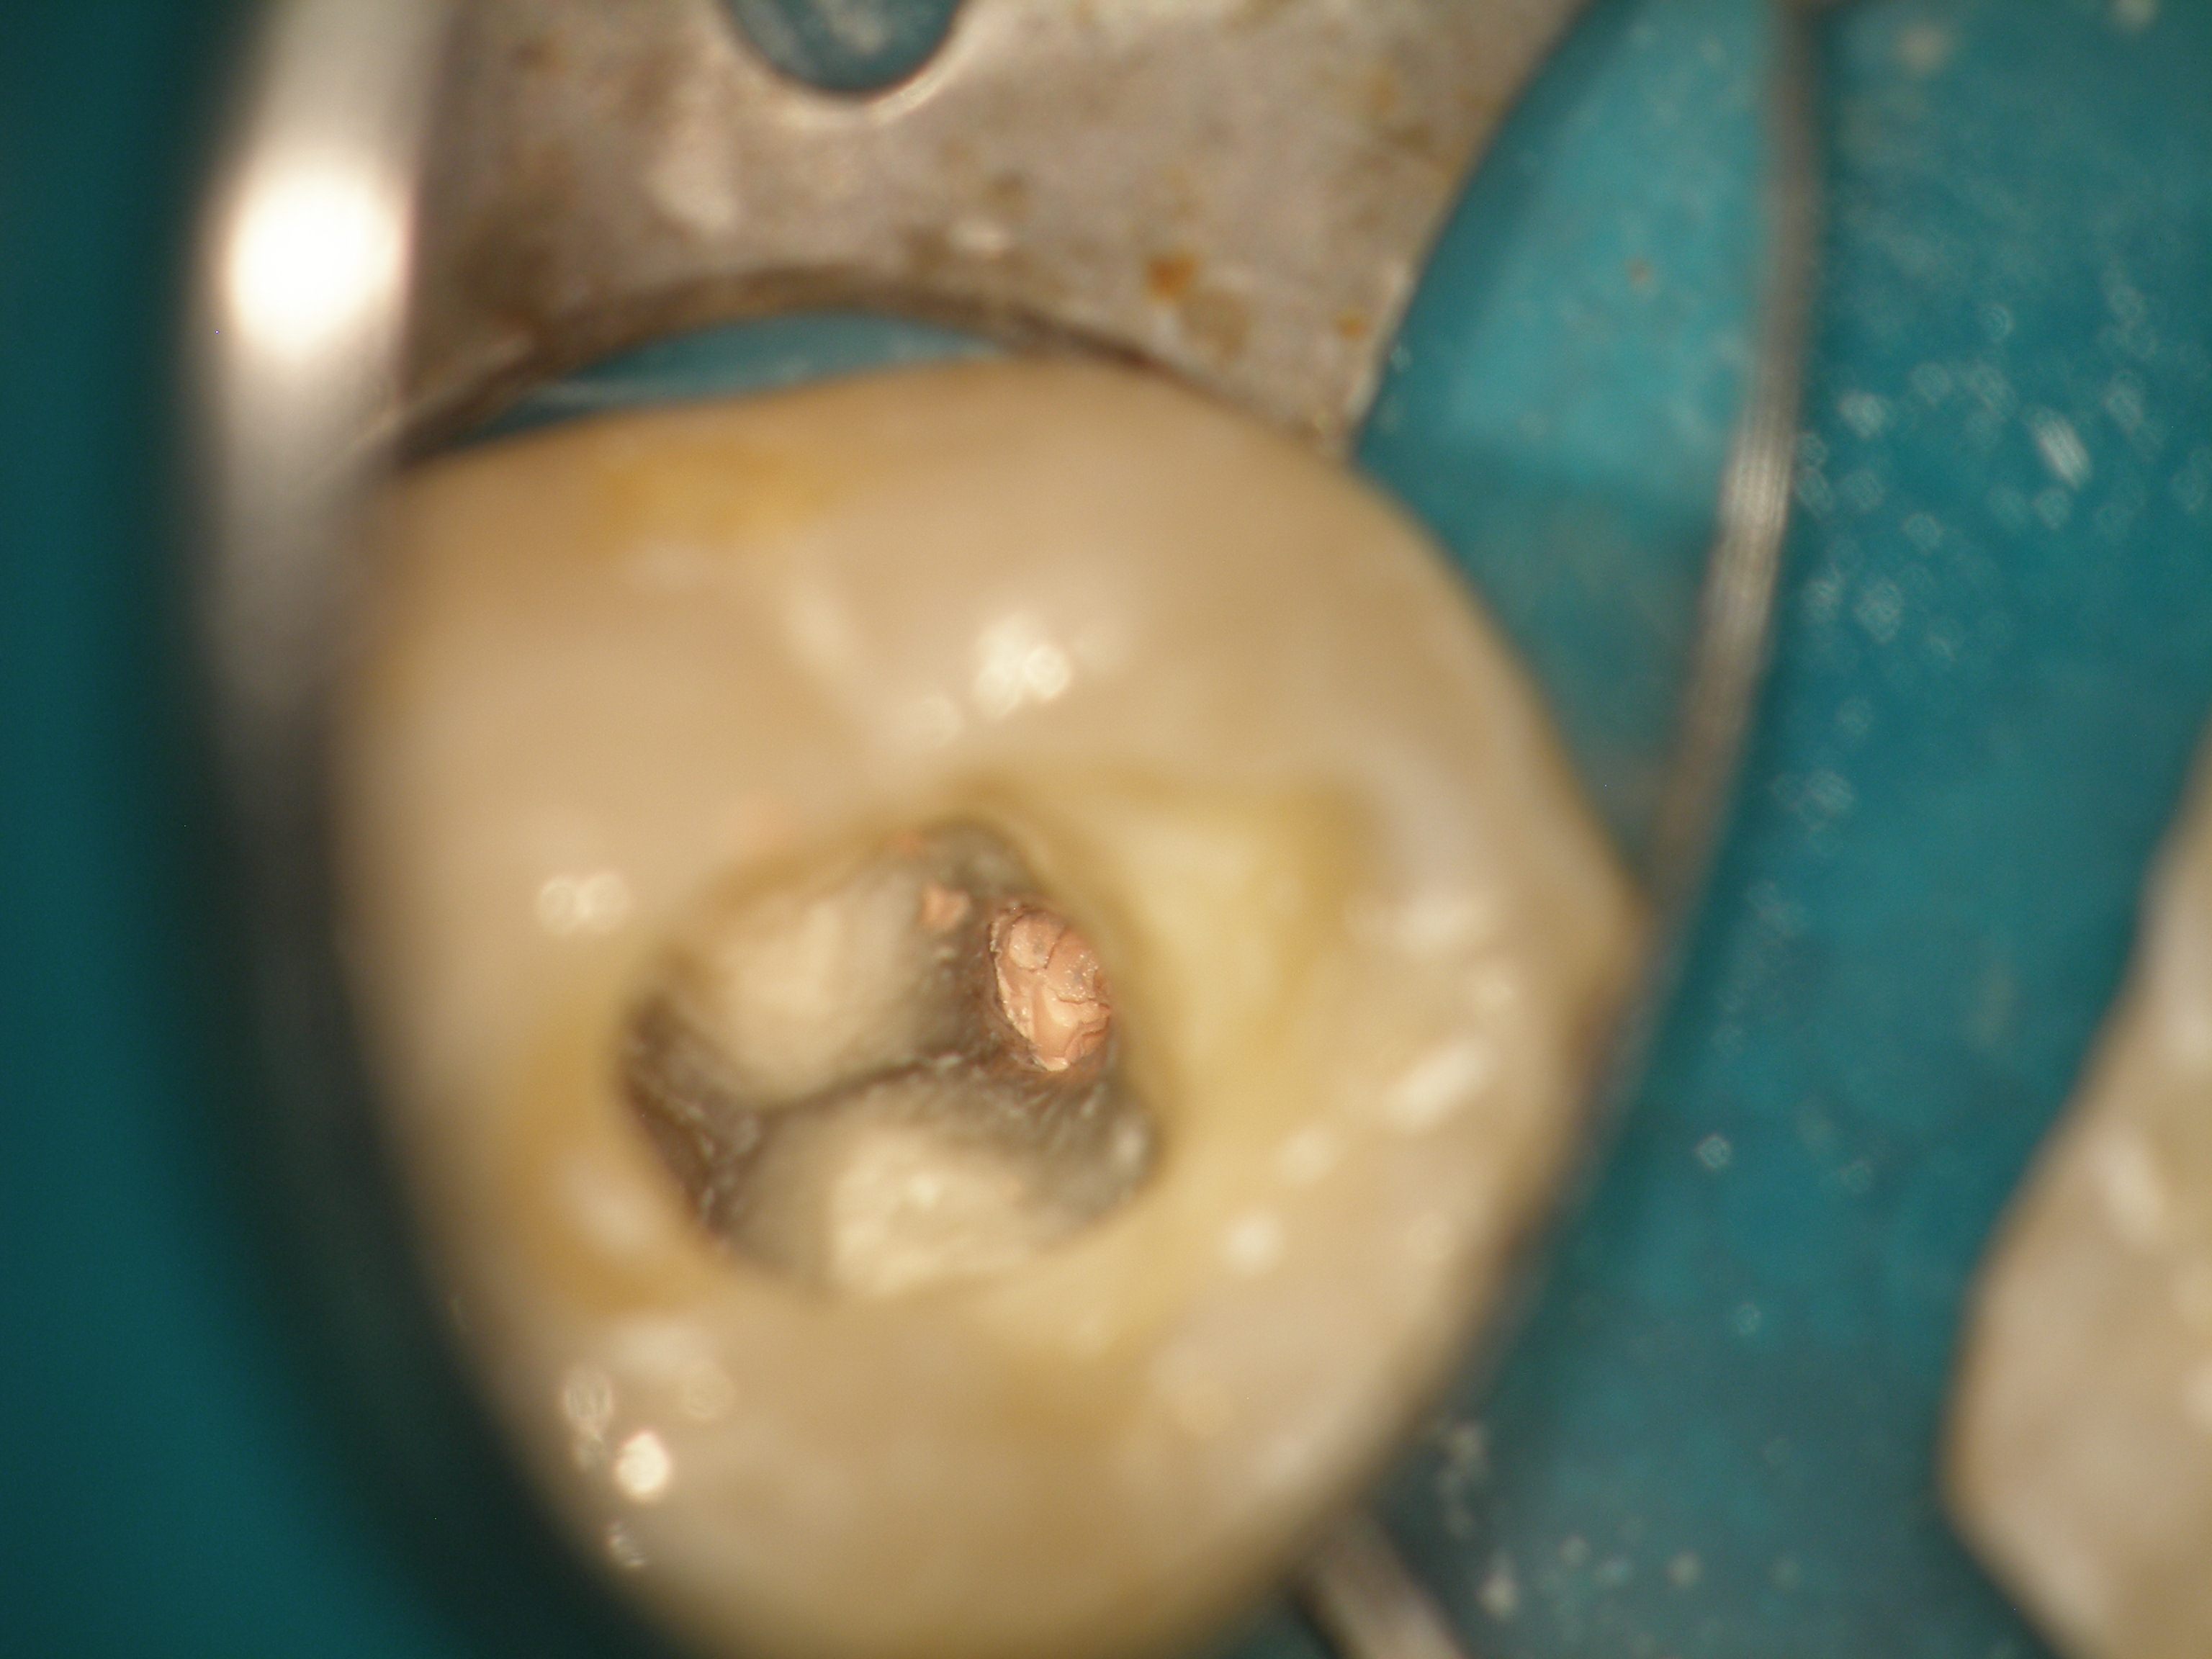

Ryc. 4. Obraz z mikroskopu zabiegowego (ząb 36). W kanale bliższym policzkowym widoczny fragment metalowego narzędzia.

1. Ząb 36 w trakcie leczenia endodontycznego, w obrębie kanałów widoczny materiał dobrze kontrastujący się na zdjęciu rentgenowskim, prawdopodobnie pasta zawierająca w swoim składzie wodorotlenek wapnia i niewielką ilość jodoformu (ryc. 1‑3). W połowie wysokości korzenia bliższego widoczny był fragment wiertła, który uległ separacji podczas preparacji łoża pod mikroimplant. Operator sperforował kanał bliższy policzkowy, pozostawiając wierzchołek narzędzia w obrębie korzenia (pierwsza próba nawiercania). Wbity w korzeń fragment był dobrze widoczny w kanale od strony jamy zęba (ryc. 4), (film 1, 2). Pacjent skarżył się na ból zęba podczas nagryzania.